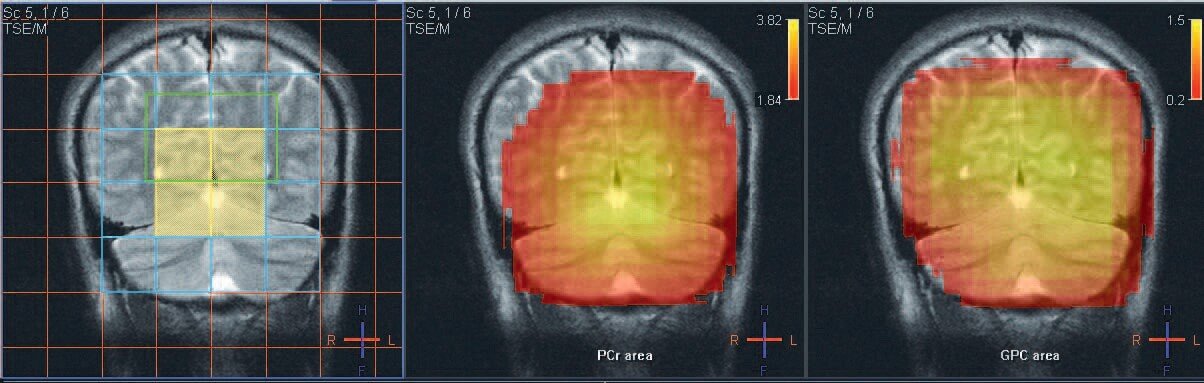

Spectroscopy